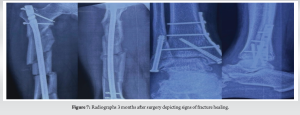

The patient had an uneventful post-operative course. An immediate post-operative radiograph depicted satisfactory alignment (Fig. 6). He was advised of early mobilisation with weight-bearing limitations . Radiographs 3 months after surgery showed signs of fracture healing and satisfactory alignment (Fig. 7). The patient continued physiotherapy to regain range of motion and strength in the injured limb. Radiographic evaluation 1 year after surgery confirmed complete fracture union (Fig. 8). The other fractures–the patella, acetabulum, cuboid, and bimalleolar–had also appropriately healed. The patient returned to his pre-injury activity level without limitations and reported no persistent pain.